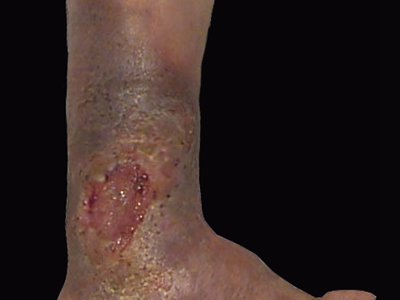

下肢深静脉血栓形成,可表现为肢体疼痛、肿胀、股青肿等,具体如下:

5、导致深静脉血栓形成后综合征:远期出现下肢肿胀、小腿皮肤色素沉着、浅静脉曲张及足靴区溃疡等。